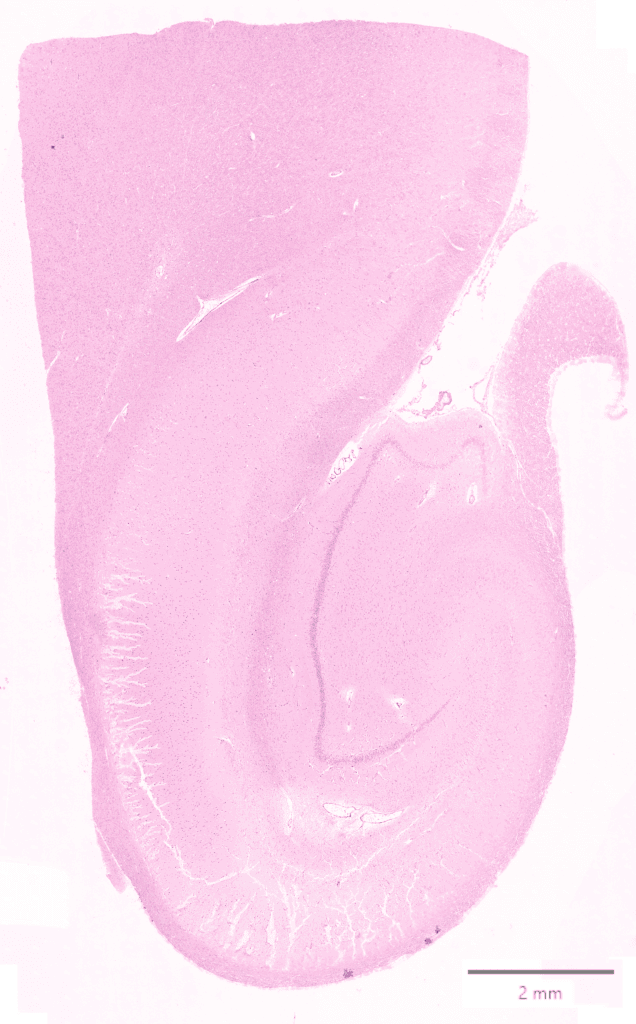

Whole transcriptome spatial data from hippocampus tissue. The immunofluorescence image below shows histone in blue, AF in green, rRNA in yellow, GFAP in red, DAPI in gray. An H&E image is also available for comparison.